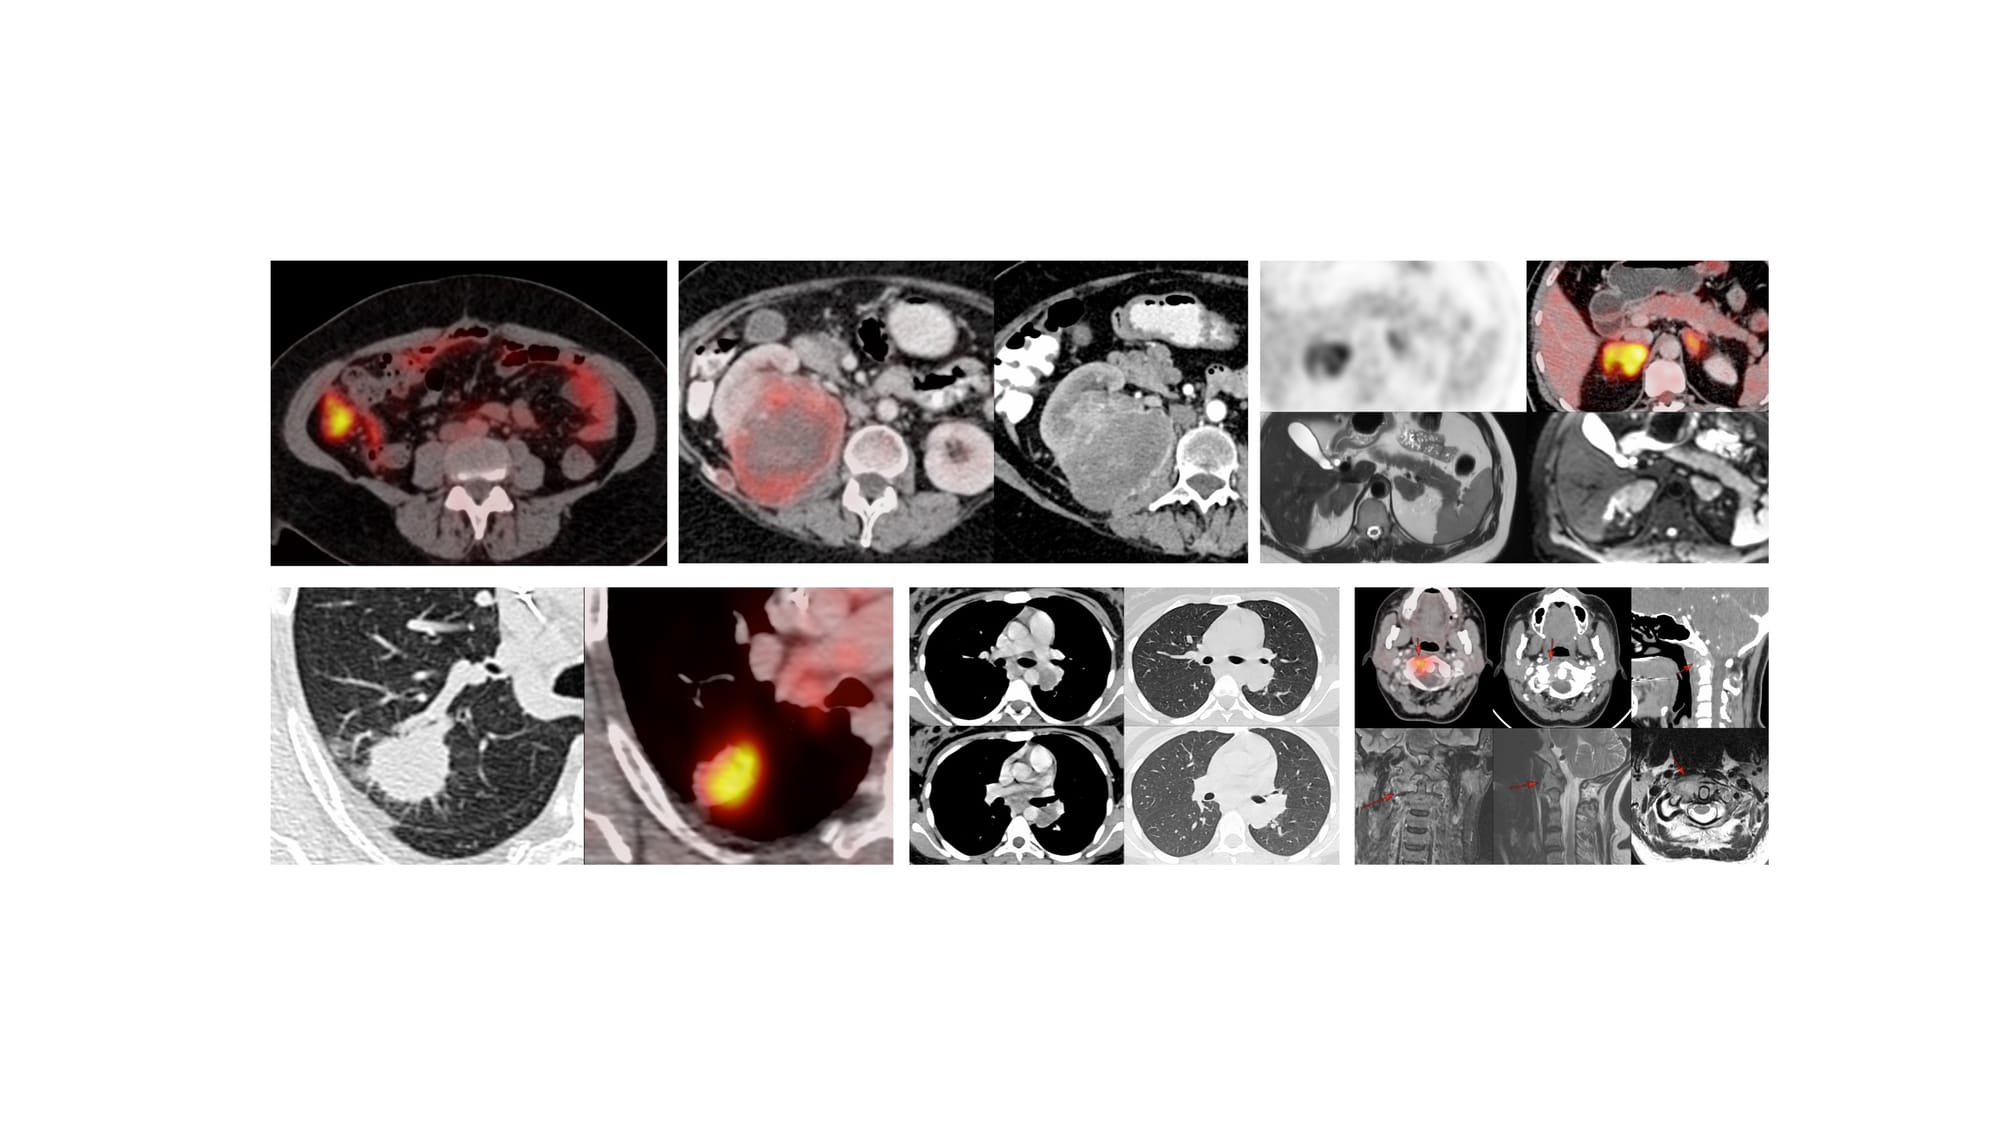

Case 172 - Right Adrenal Gland Biopsy Using an Ipsilateral Up Approach with Hydrodissection

Bhavin Jankharia - 31 December 2025

Case 171 - Splenic Mass Biopsy

Bhavin Jankharia - 04 December 2025

COD 127 - Maxillary Sinus Biopsy

Bhavin Jankharia - 09 November 2025

Case of the Day 106 - 2025 09 22 - Retroperitoneal Posterior Parapsoas Approach - Macrocystic Lymphatic Malformation Aspiration

Bhavin Jankharia - 02 October 2025

Case of the Day - 098 - 2025 09 08 - Confirming Tuberculosis of the Lower Cervical Spine

Bhavin Jankharia - 09 September 2025